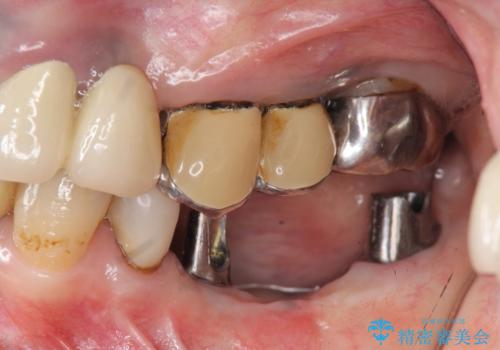

- 左下に長年使用した入れ歯が合わず、よりしっかりと噛みたいという希望で来院されました。

入れ歯をはずししっかりと噛む手段としてインプラント治療を進めていきます。

- 90万円(ストローマンインプラント×2・チタンカスタムアバットメント×2・ジルコニアクラウン×3)費用は治療当時の料金となります

インプラントを用いることで、たくさん失ってしまった奥歯を入れ歯よりもしっかりと噛む状態へと回復することができます。